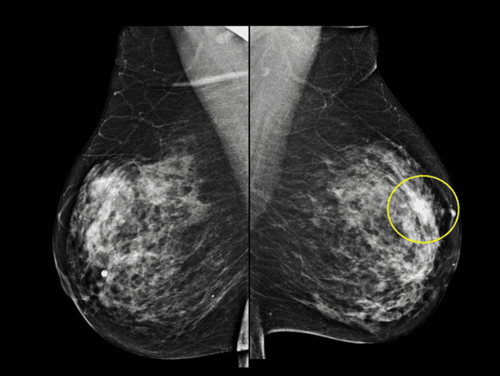

Hình ảnh ung thư da

Ung thư da thường bắt đầu với những thay đổi trên làn da. Chúng có thể là sự tăng trưởng mới hoặc tổn thương tiền ung thư. Ung thư da có thể được chữa khỏi nếu được phát hiện và điều trị sớm.